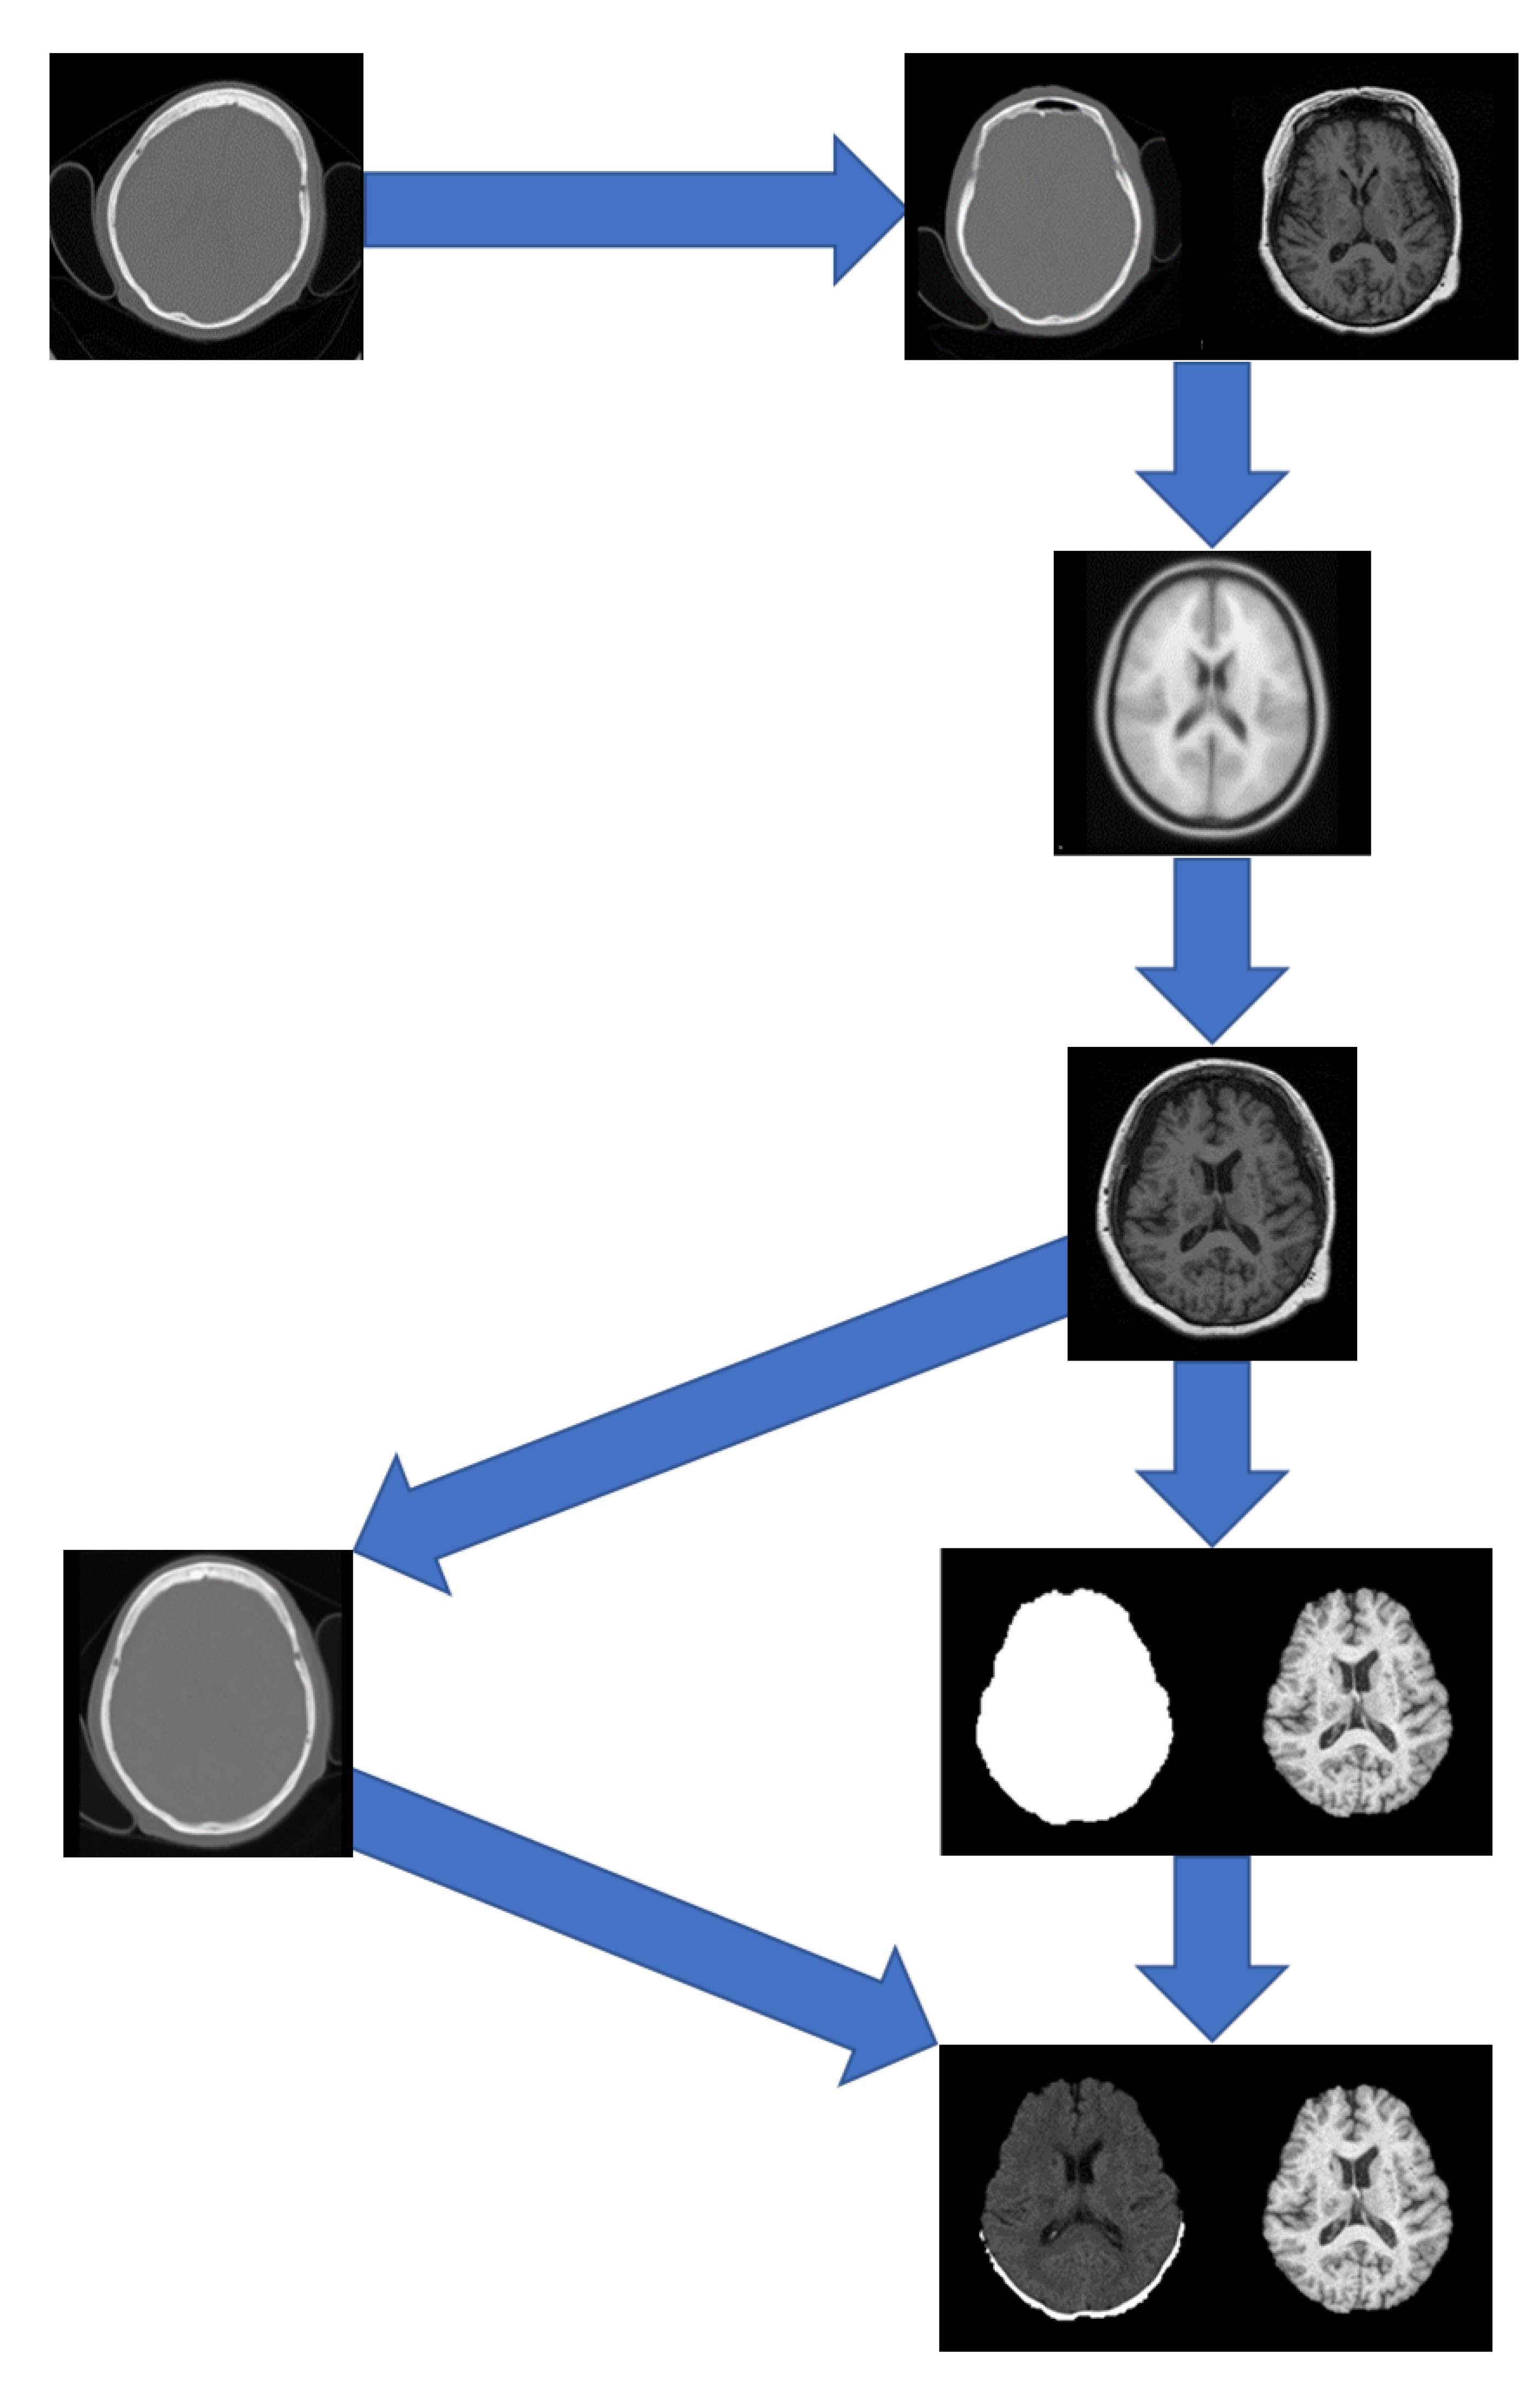

A pipeline was developed to pre-process the data which included registration to a brain atlas and brain extraction. The following steps detail the pre-processing pipeline (Figure 1):

• Registration of the CT to the MRI using FSL Flirt [24,25,26] with 12 degrees of freedom and a mutual information cost function.

• Registration of the MRI to the ICBM152 T1w linear atlas using FSL Flirt [24,25,26] with 12 degrees of freedom and a correlation ratio cost function, and saving the transformation matrix.

• Applying the transformation matrix from step 2 to the resultant CT from step 1.

• Apply the runhdbet function of HD-BET [27] to the resultant MRI from step 2. The resultant extraction brain and brain mask are then saved.

• Using pixelwise multiplication between the resultant CT scan from step 3 and the brain mask from step 4 to extract the brain from the CT.

Figure 1. Preprocessing pipeline showing registrations of the CT to MRI and the MRI to MNI152 followed by brain extraction.